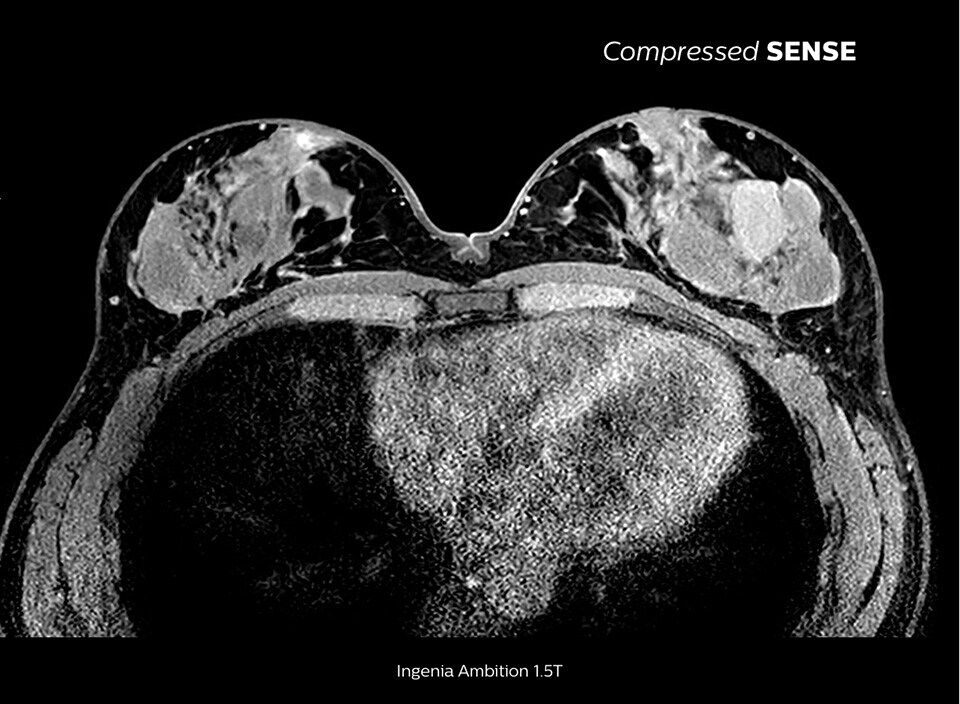

Learn more about the main principles of Compressed SENSE MRI software and how it introduces a paradigm shift in productivity. Compressed SENSE was designed around image quality, and it can accelerate scans, increase spatial resolution and enhance the patient experience for clinical MR imaging.

The MRI staff at Kurashiki Central Hospital incorporated Compressed SENSE into most of the brain, spine, abdominal, and cardiac examination protocols on their Ingenia 1.5T, resulting in fast and high-quality MRI scans, which is welcomed by patients and staff.